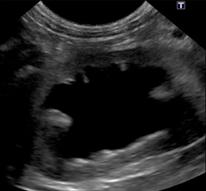

尿管結石による水腎症

体質、食事、尿路感染などにより結石が形成されます。腎臓、尿管、膀胱、尿道に存在し、尿管や尿道が詰まると重篤な症状を呈する場合があり注意が必要です。結石の存在している場所で治療が異なりますが、尿路閉塞がみられる場合は早急な処置、手術が必要となります。膀胱結石の場合は食事療法で結石が溶ける場合もあります。